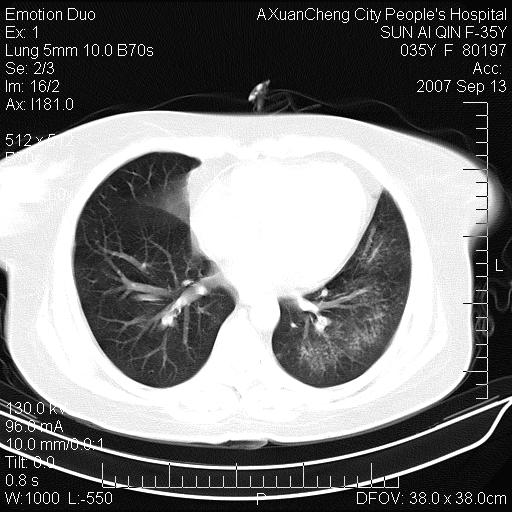

以下是引用天南地北在2007-9-13 13:43:00的发言:[br]考虑双肺、肺门侵润

以下是引用ydx_74在2007-9-13 15:42:00的发言:[br]仅看片,考虑右上肺癌并双肺转移,结合病史,考虑肺门、肺内淋巴侵润

以下是引用同在2007-9-13 15:08:00的发言:[br]支持肺门及双肺侵润.